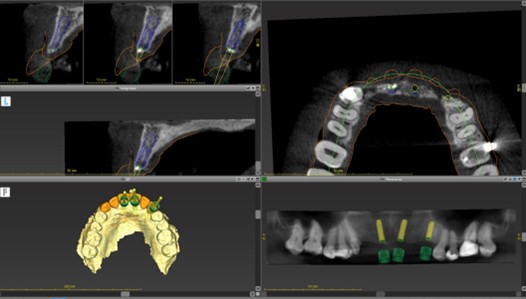

精密検査の画像データをもとに、専用ソフトでインプラントの最適な位置や角度を決定します。CT(歯と骨)と3Dスキャナ(歯と歯肉)のデータを組み合わせ、より正確な治療計画を作成。問題なければ、サージカルガイドの設計・作製へ進みます。